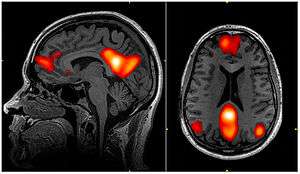

In neuroscience, the default mode network (DMN), (also default network, or default state network), is a network of interacting brain regions known to have activity highly correlated with each other and distinct from other networks in the brain.[3]

The default mode network is an interconnected and anatomically defined[3] set of brain regions. The network can be separated into hubs and subsections:

Functional hubs:[15] Information regarding the self

- Posterior cingulate cortex (PCC) & precuneus: Combines bottom-up (not controlled) attention with information from memory and perception. The ventral (lower) part of PCC activates in all tasks which involve the DMN including those related to the self, related to others, remembering the past, thinking about future, and processing concepts plus spatial navigation. The dorsal (upper) part of PCC involves involuntary awareness and arousal. The precuneus is involved in visual, sensorimotor, and attentional information.

- Medial prefrontal cortex (mPFC): Decisions about self processing such as personal information, autobiographical memories, future goals and events, and decision making regarding those personally very close such as family. The ventral (lower) part is involved in positive emotional information and internally valued reward.

- Angular gyrus: Connects perception, attention, spatial cognition, and action and helps with parts of recall of episodic memories

The default mode network is most commonly defined with resting state data by putting a seed in the posterior cingulate cortex and examining which other brain areas most correlate with this area.[16] The DMN can also be defined by the areas deactivated during external directed tasks compared to rest.[17]